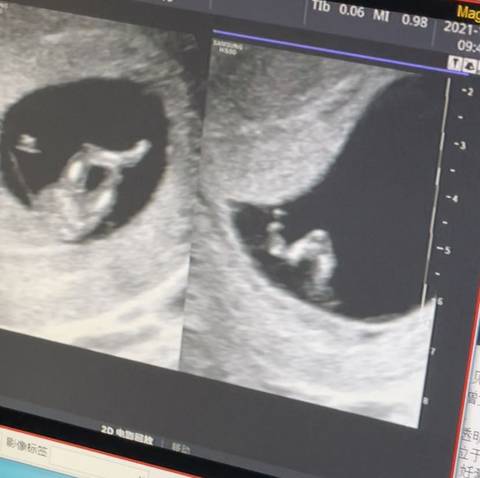

大伙能看看是男宝还是女宝吗 我这是一胎男女都爱哈!

journal_insert_pic_1676707298journal_insert_pic_1676707304journal_insert_pic_1676707317

你好。我们是判断不了男宝宝跟女宝宝的,孕期定期检查,我觉得宝宝健康就好的。祝心想事成 。